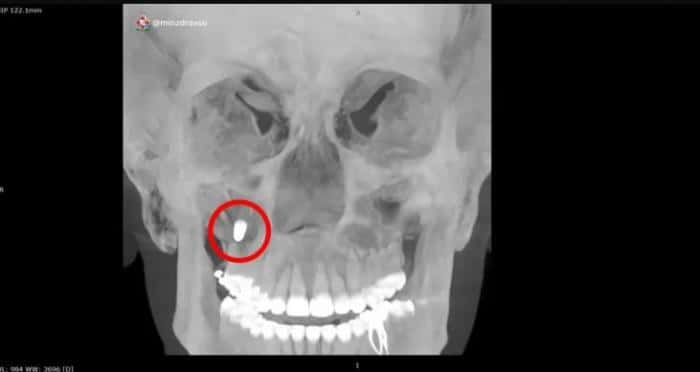

Фото: Пресс-служба минздрава Свердловской областиВрачи Екатеринбурга провели уникальную операцию, спасая пациентку, у которой зубной имплант оказался в гайморовых пазухах. Протез мигрировал туда после неудачно проведенной стоматологической операции несколько месяцев назад, сообщили в пресс-службе регионального минздрава.

«Специалисты многопрофильного клинического медицинского центра „Бонум“ выполнили сложное эндоскопическое удаление металлического импланта из верхних отделов гайморовых пазух», — уточнили в ведомстве. До этого протез был протолкнут в правую верхнечелюстную пазуху.Операция была проведена через полость носа с использованием эндоскопической техники. Этот метод позволил избежать травматичных разрезов за губой и повреждения передней стенки пазухи. Вмешательство прошло успешно, и сейчас пациентка чувствует себя хорошо.